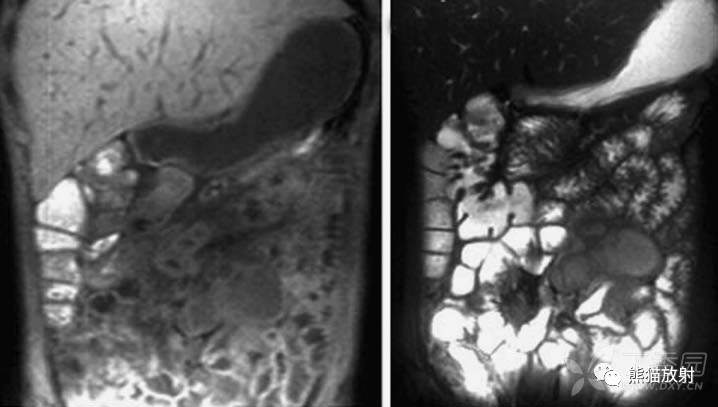

结核性腹膜炎。大网膜增厚,腹水,肠袢外移

结核性腹膜炎。小肠轻度扩张并肠环间距增加

结核性腹膜炎。大网膜增厚,腹水